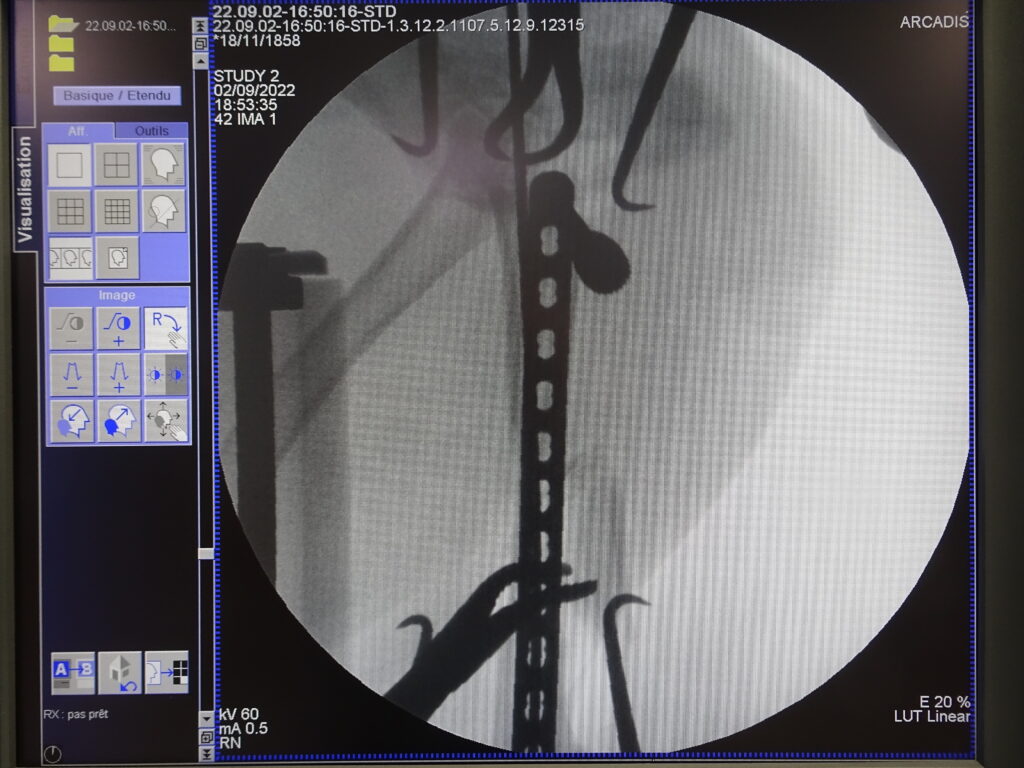

Stabilisation d’une fracture du fémur par voie mini invasive grâce à la fluoroscopie.